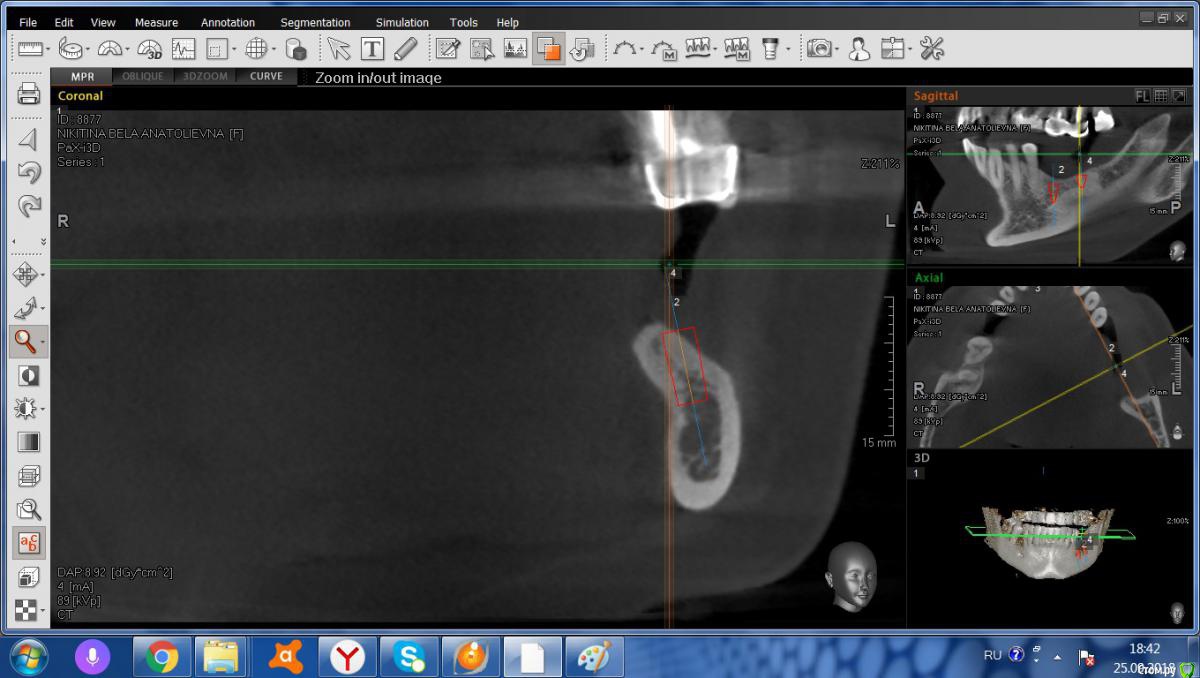

kamranchick Опубликовано 25 сентября, 2018 Поделиться Опубликовано 25 сентября, 2018 вот Ссылка на комментарий

kamranchick Опубликовано 26 сентября, 2018 Поделиться Опубликовано 26 сентября, 2018 думаю вот на таком варианте остановится Ссылка на комментарий